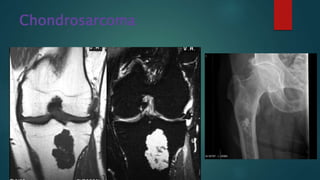

Chondrosarcoma